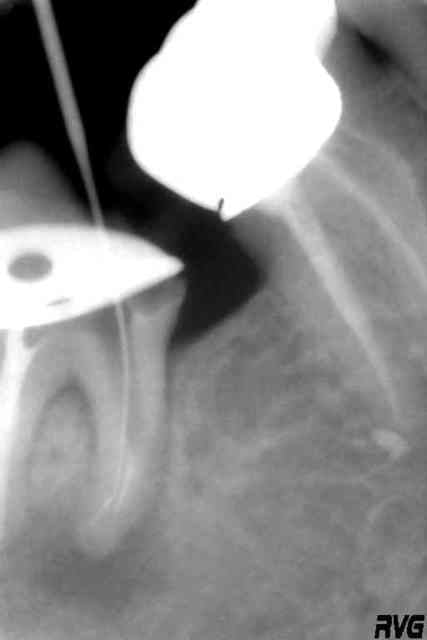

radios

R1 uq8spw - Eugenol

R2 hscwt1 - Eugenol

R3 bceowk - Eugenol

R4 vrw98y - Eugenol